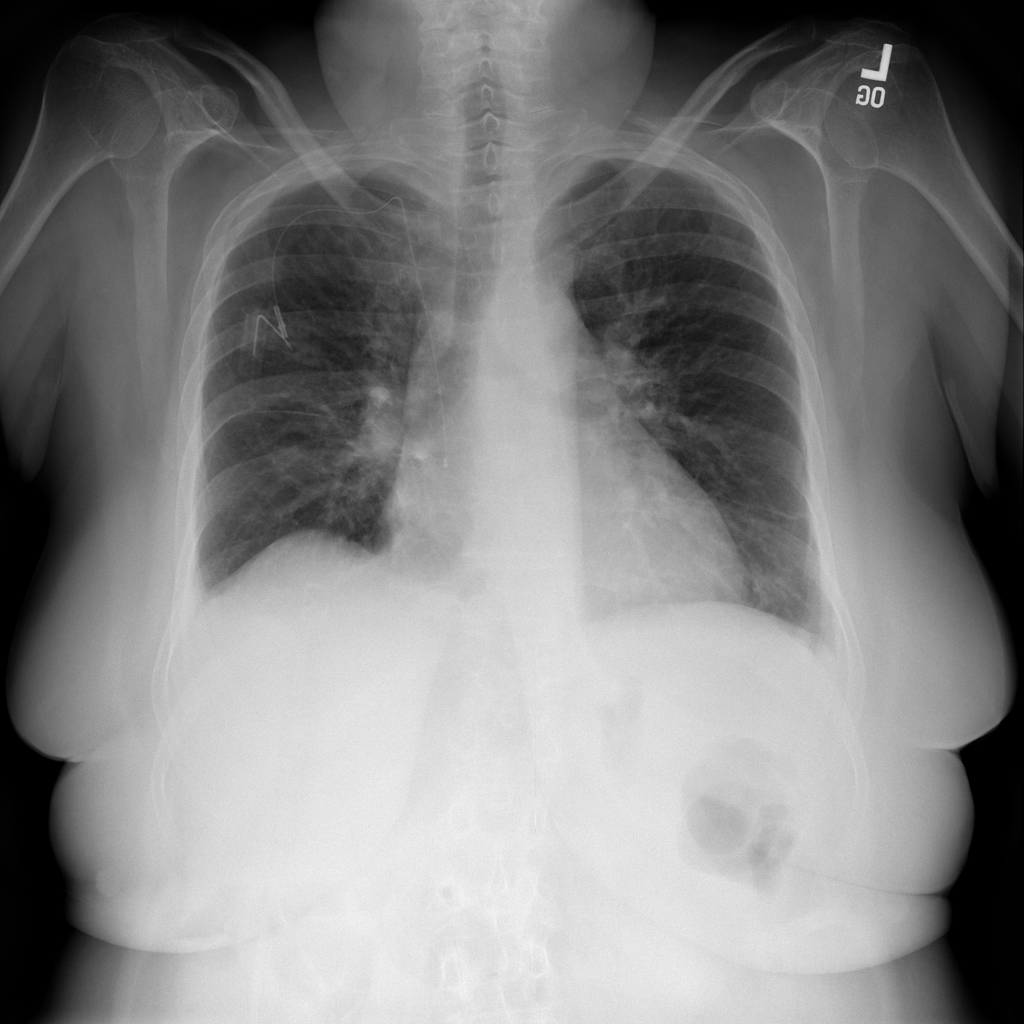

PAT-E828 · IMG-005Edema

PAT-E828 · IMG-005

AP